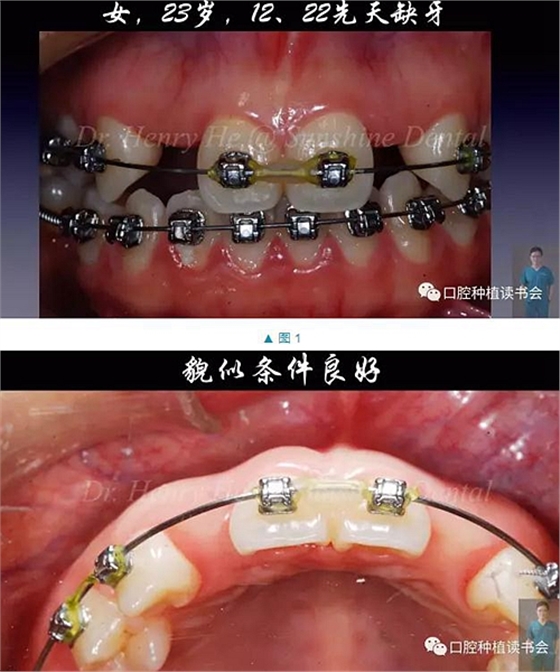

本臨床病例報告的患者為23歲的年輕女士,先天缺失12,22,為了給種植治療創(chuàng)造空間,2年前開始在外院正畸;正畸醫(yī)生認為修復(fù)空間調(diào)整到位后,告知患者可行種植治療。

口內(nèi)檢查發(fā)現(xiàn):患者口腔衛(wèi)生良好,牙周健康,除了12,22缺失外,未見其它問題。12,22缺隙近遠中大小約為8mm,臨床冠空間足夠(圖1,2)。患者中位笑線,中厚齦生物型,美觀要求很高(圖3)